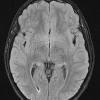

NEOPLASMS (HEMATOLYMPHOID)

Langerhans Cell Histiocytosis (LCH) (9)